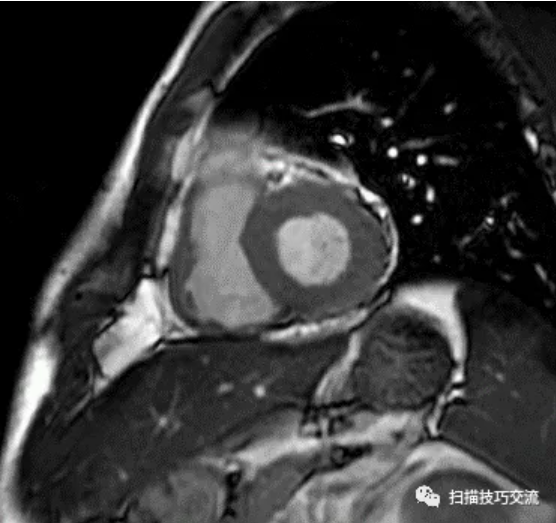

有人说,会不会是脂肪

FIESTA电影,收缩期末

FIESTA电影,舒张期末 相同位置,并未发现脂肪高亮信号。 补充病史: 一、 CTA提示:LCX中段90%狭窄。 这与磁共振的MDE序列相吻合。